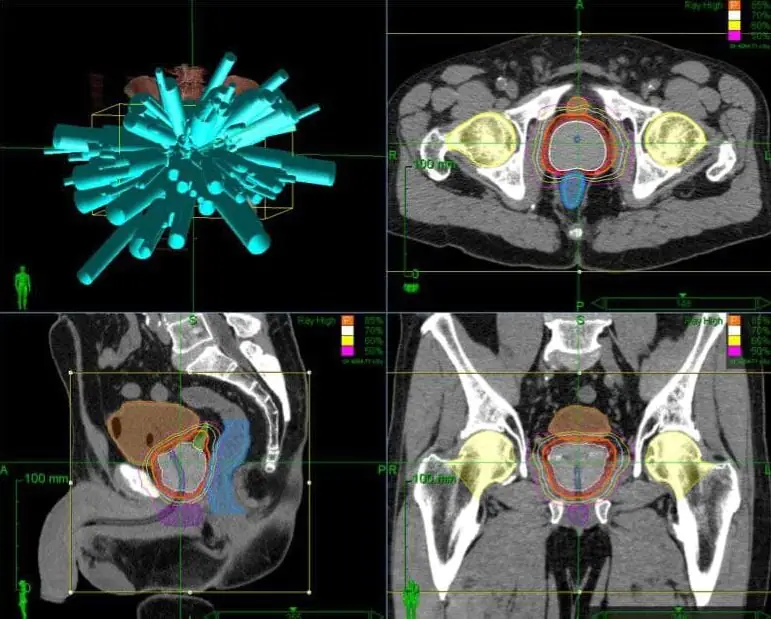

Лечение метастаза рака кишечника в печени кибер-ножом

МРТ-исследование метастаза рака кишечника в печень

На ПЭТ-КТ выявляется биологическая активность в центре опухоли

МРТ печени через 8 недель после лечения. Терапия была проведена под контролем фаз дыхания Киберножом. Опухоль разрушена, центральный некроз, реакция окружающих тканей минимальна